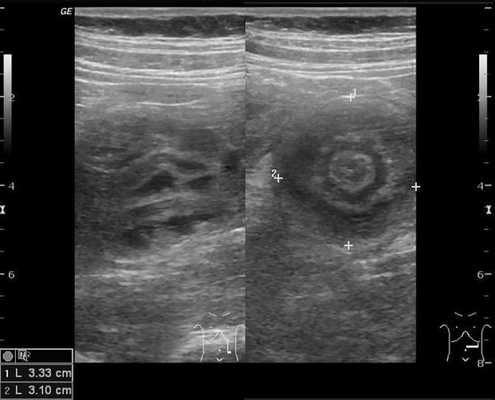

Для визуализации инвагината проводится УЗИ брюшной полости: определяется гипоэхогенное образование с участком гиперэхогенности в центральной части. Также может применяться ультразвуковая допплерография с целью оценки кровотока в сосудах брыжейки. Обзорная рентгенография брюшной полости обладает меньшей чувствительностью при обнаружении инвагината, но применяется как скрининговый метод исследования при острой боли в животе с целью исключения перфорации, обструкции.

В момент УЗ-исследования врач может определить один из симптомов:

- симптом мишени (за счёт внедрения одной кишки в другую инвагинат на срезе выглядит как мишень);

- симптом "почки с завоздушенным центром".